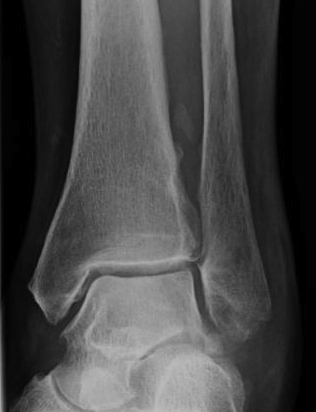

X-ray

Changes occur 2-4 / 52 after injury

Initial cotton candy appearance

- then osseous in appearance

- not attached to bone

- can be resorbed

Mature bone peripherally